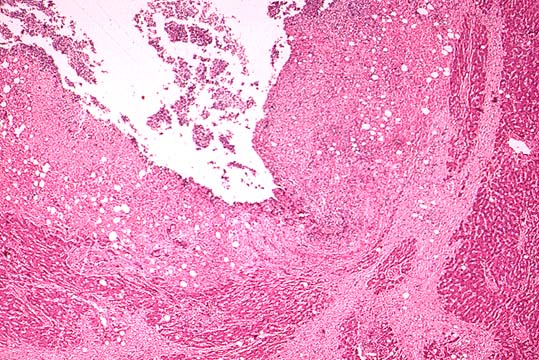

Fig.136-Pyogenic liver abcess

Cavity of a large abscess due to diverticulitis of the sigmoid colon apparently present for some time because the cavity is surrounded by a considerably thick fibrous capsule.